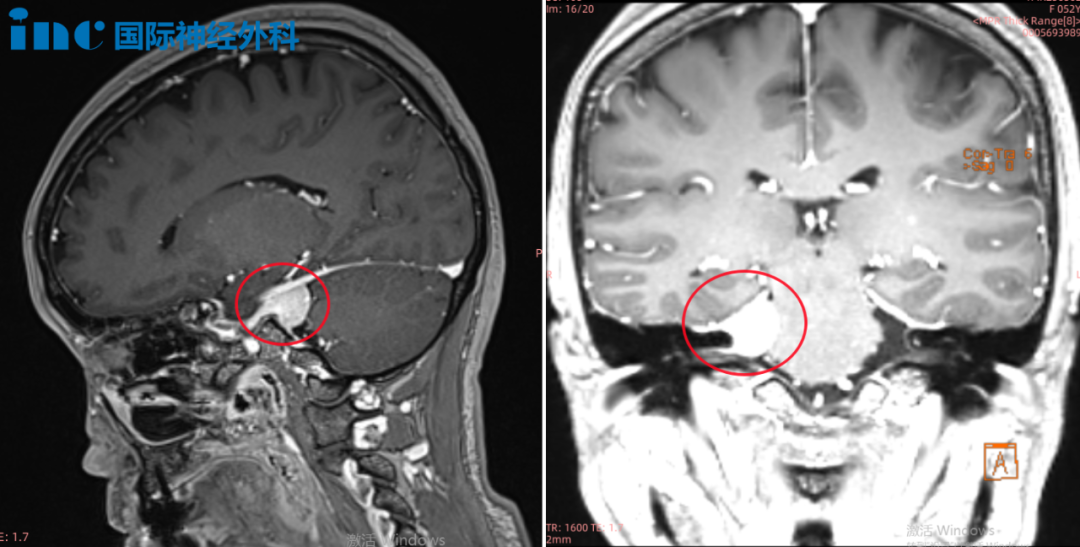

▼術(shù)前術(shù)后MRI對比

術(shù)前術(shù)后MRI對比

2022年,巴教授中國行中,巴教授成功主刀手術(shù)腫瘤全切,無新發(fā)神經(jīng)功能損傷。

術(shù)后第一天ICU查房,鐘女士狀態(tài)清醒,和教授交流順暢。術(shù)后第五天查房,鐘女士狀態(tài)良好,連聲感謝巴教授并和教授開心合影。病理結(jié)果腦膜瘤WHOI級,良性預(yù)后很好,術(shù)后將不再需要反復(fù)放化療,她可以像正常人一樣生活。術(shù)后2年,復(fù)查核磁無復(fù)發(fā)。